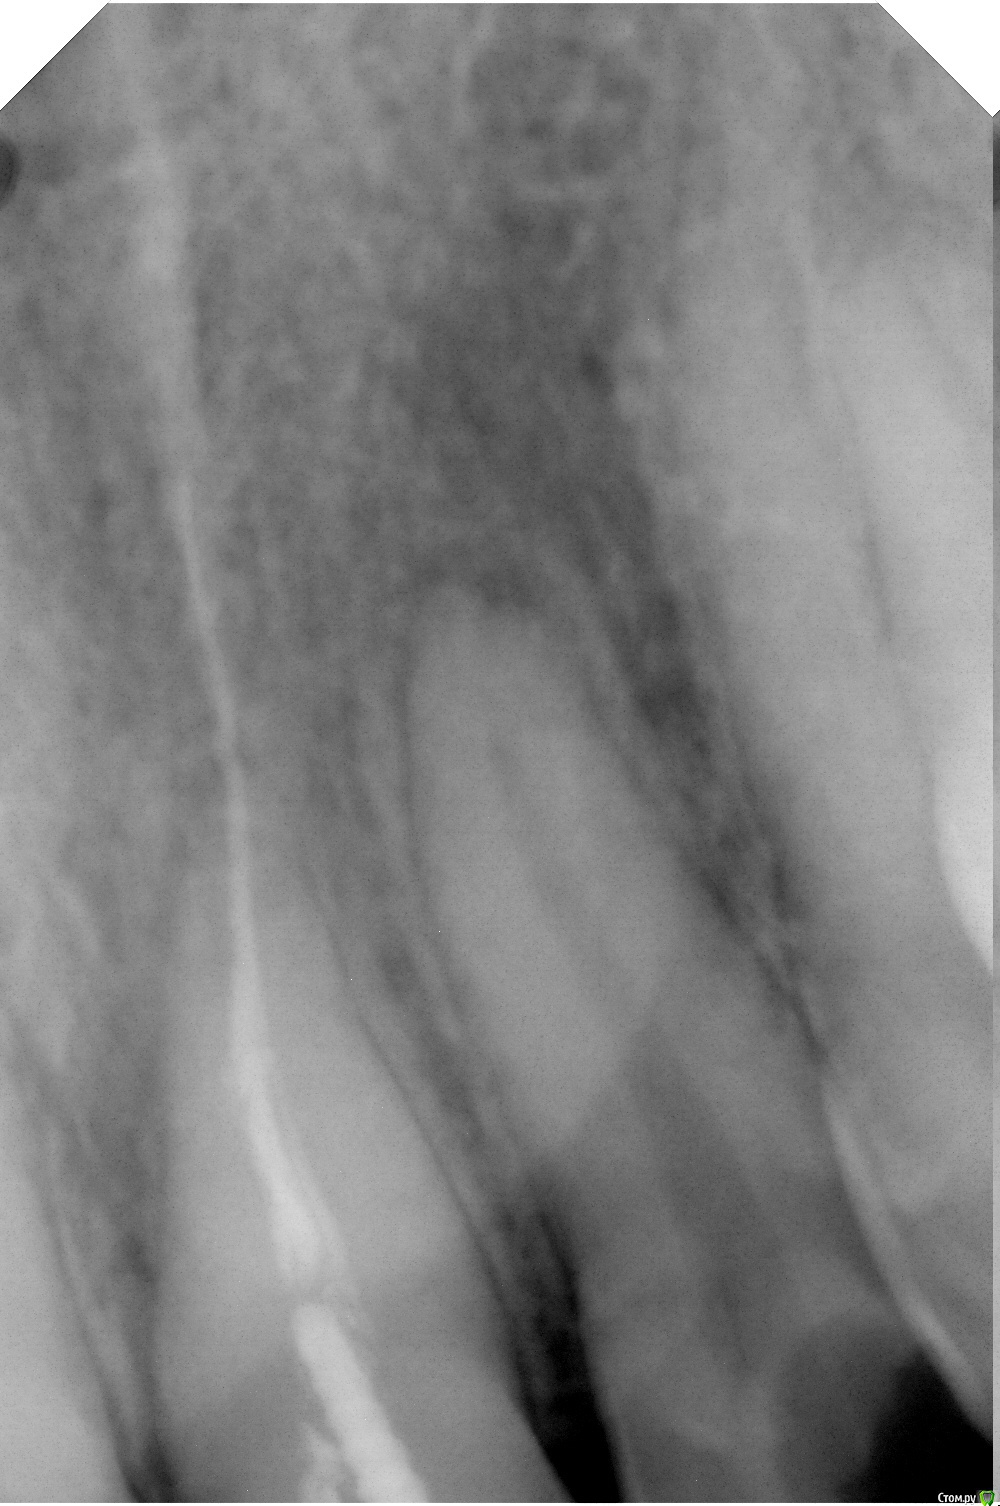

Ultron Опубликовано 16 января, 2016 Поделиться Опубликовано 16 января, 2016 Три месяца назад сделал реставрацию 21ого зуба на штифт. Сейчас у корня зуба образовался плотный мешочек, на зубе чувствуется распирание, были небольшие боли при касании языком, но они быстро прошли. Чего ожидать от визита к врачу и как можно протянуть до понедельника? Зуб беспокоит не сильно, но осложнений допустить не хотелось бы. Ссылка на комментарий

DmitrySH Опубликовано 16 января, 2016 Поделиться Опубликовано 16 января, 2016 По снимку у соседнего зуба есть проблемы со здоровьем, он не беспокоит? Ссылка на комментарий

Гарриевич Опубликовано 17 января, 2016 Поделиться Опубликовано 17 января, 2016 (изменено) Проблема и в том зубе где штифт и в соседнем Изменено 17 января, 2016 пользователем Гарриевич Ссылка на комментарий

red_butler Опубликовано 17 января, 2016 Поделиться Опубликовано 17 января, 2016 Соседний зуб был сломан недавно, но он не беспокоит. А в чем конкретно проблема и чего ждать?Похоже - периодонтит. Ждать обострения. Ссылка на комментарий